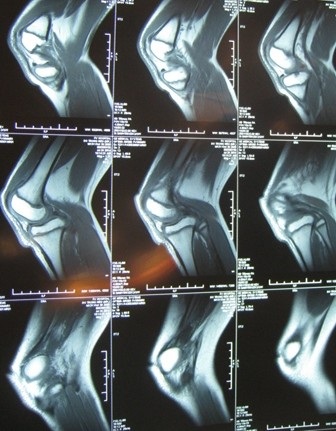

Sau khi tiếp nhận bệnh nhân, TS.BS Lê Trọng Phát, Trưởng khoa chấn thương chỉnh hình, Bệnh viện FV tiến hành kiểm tra và xác định: Xương bánh chè của bệnh nhi trật hoàn toàn ra ngoài, khớp gối chày bị bán trật. Gân bánh chè và một số dây chằng dính nhau, chéo trước, chéo sau thành một khối bùi nhùi, giãn dây chằng chéo trước, thiếu sàn sụn chêm ngoài khớp gối, có cuộn hoạt dịch dưới xương chày... Đây là một dị tật bẩm sinh rất hiếm gặp.